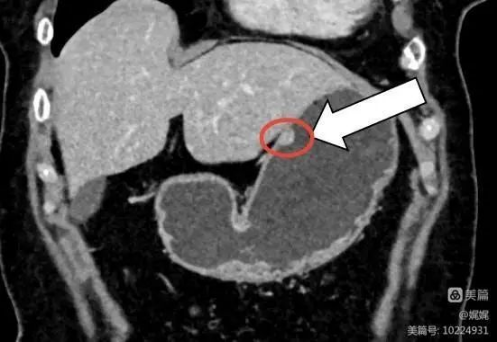

水作为一种阴性对比剂,大量喝水可以让胃肠道充分充盈,有利于胃及肠壁病灶的检出。前面蓝圈圈和黄圈圈出部分为“胃”,像一个气球样结构,可以看出黄圈圈中胃在“充分饮水”的情况下,才能把胃壁“撑开”成较薄的一层,如果胃壁有较小肿瘤或异常增厚,就可以很清楚的发现;而蓝圈圈里的胃饮水不足,胃壁不能充分“撑开”,显示胃壁皱缩较厚,不容易看清楚胃壁是否有病变,影响检查结果的准确性。

图上红圈圈里是在足量饮水时在胃壁上看到的小病变 到这里,是不是问题又来啦?既然喝不喝水对结果的影响这么大,那么到底要喝多少水才是足量饮水呢? 答案是500ml~1000ml,也就是我们平时看到的那种1~2瓶矿泉水的量。正常人饱腹状态时,胃容量能达到1200ml~1600ml,所以检查的时候要尽量把胃撑开,会更有助于影像诊断。 温馨小贴示:急性胰腺炎、肠梗阻等有饮水禁忌的患者,腹痛严重的急腹症患者,可以不用饮水,尽快检查,以免耽误治疗时机,加重病情!